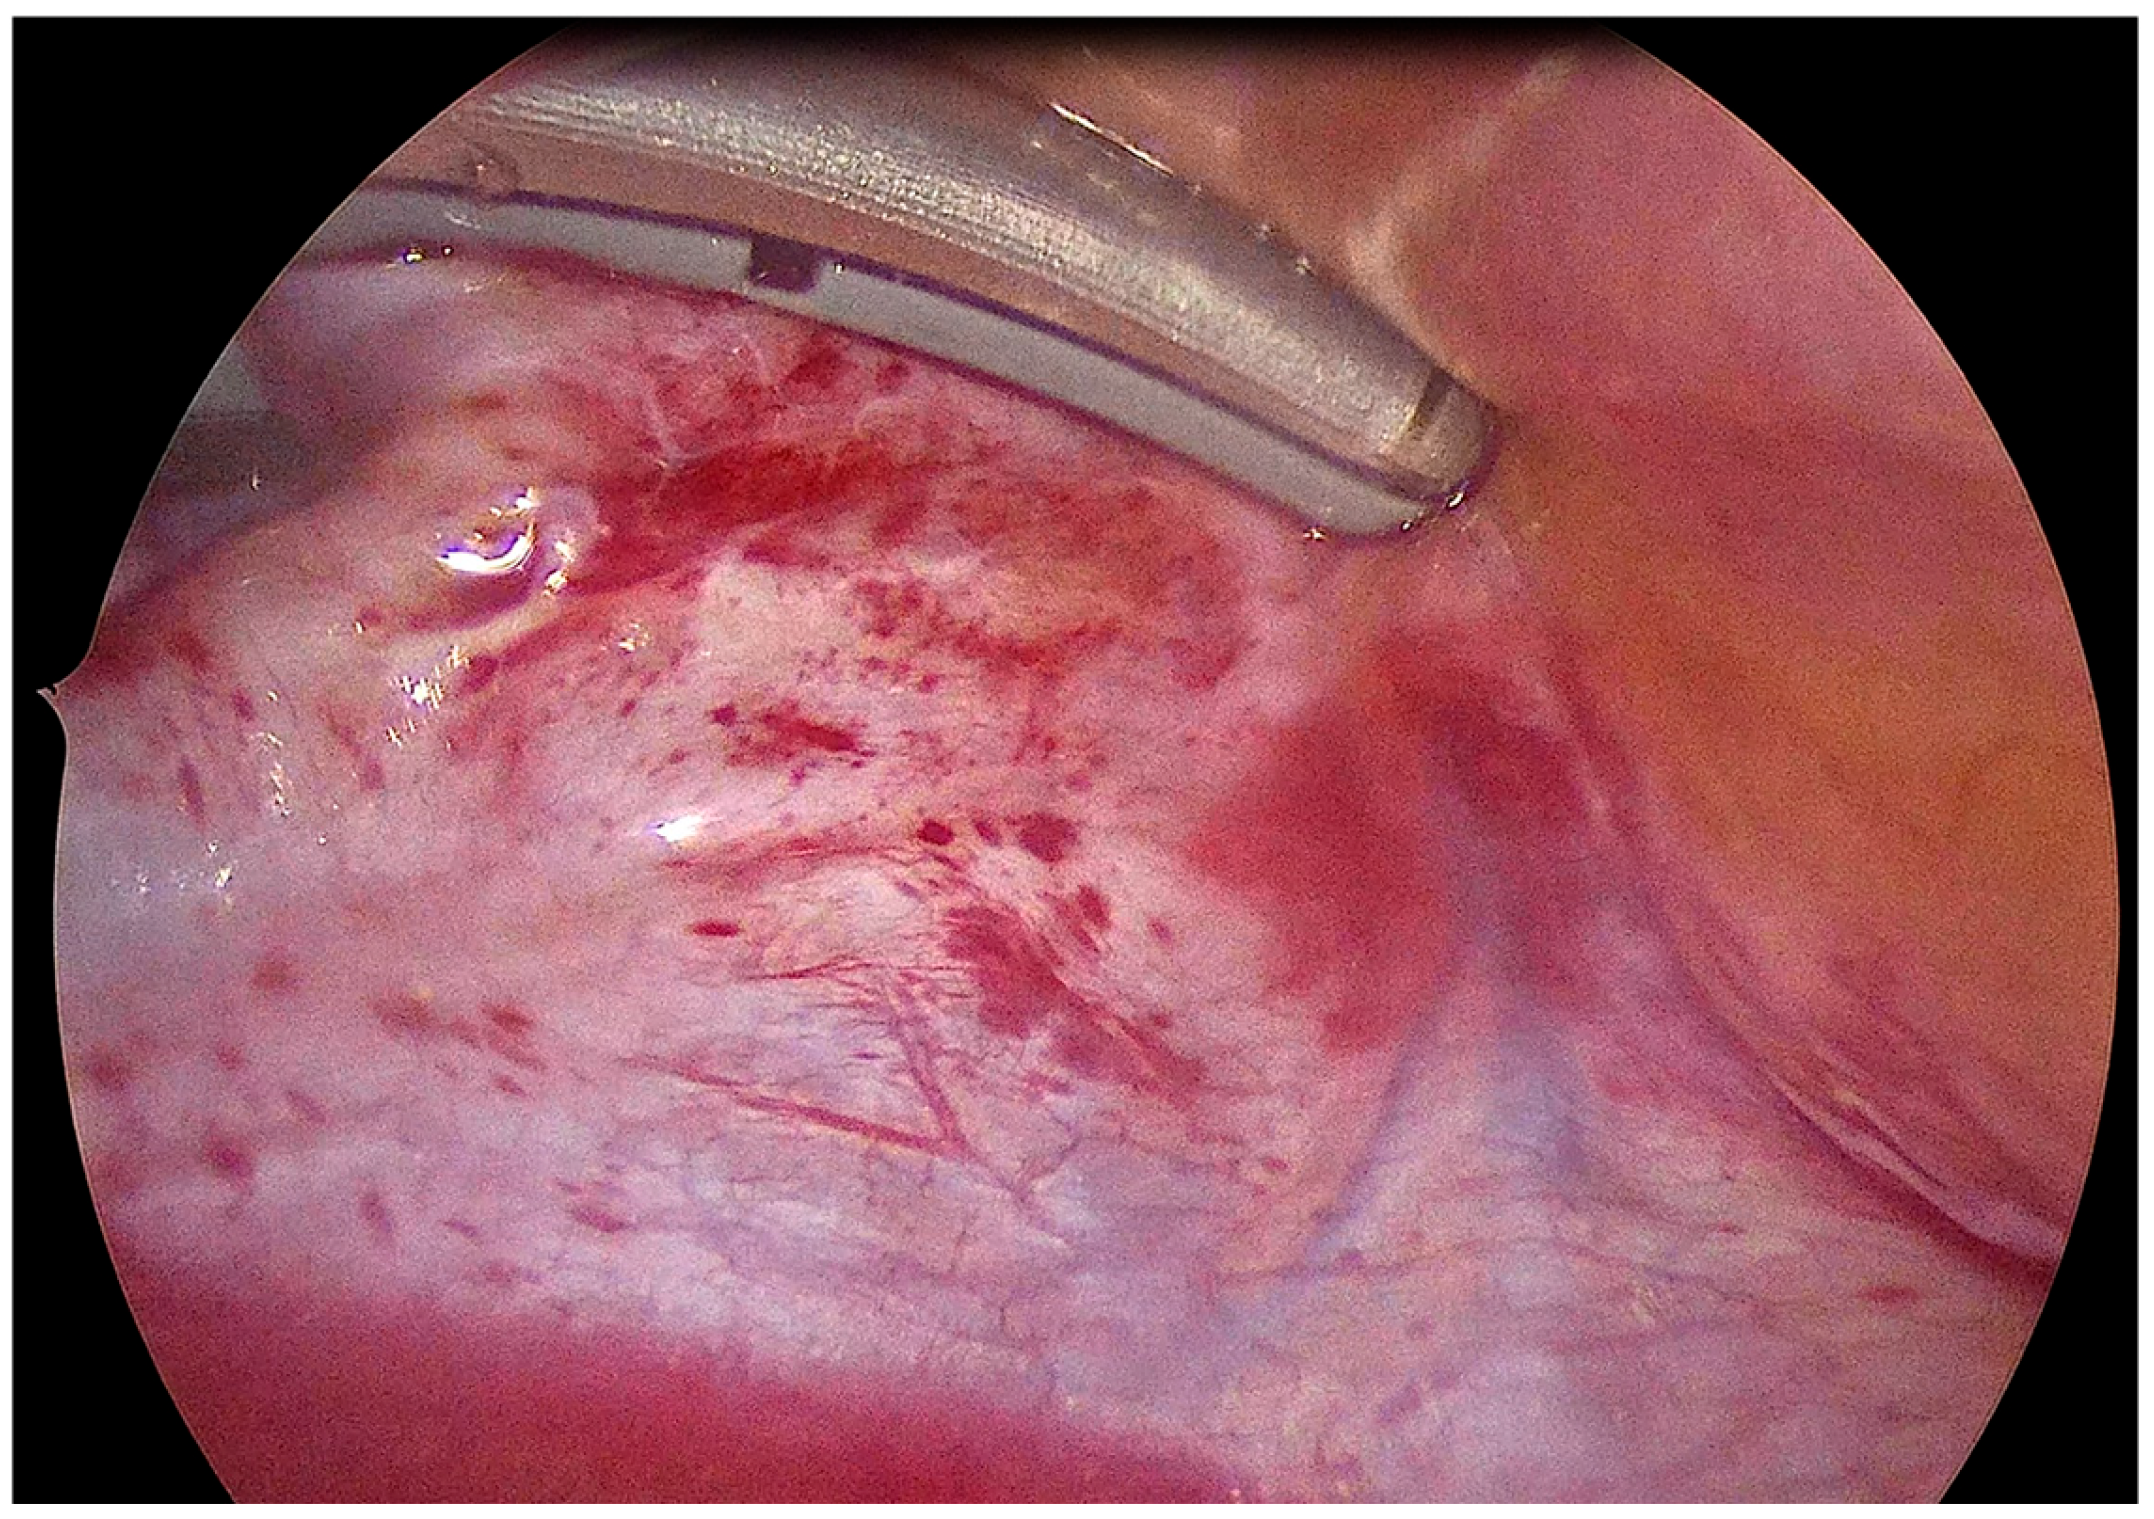

2.2. Surgical Procedure

3.2. Intraprocedural Assessment of Epicardial Lesion Set